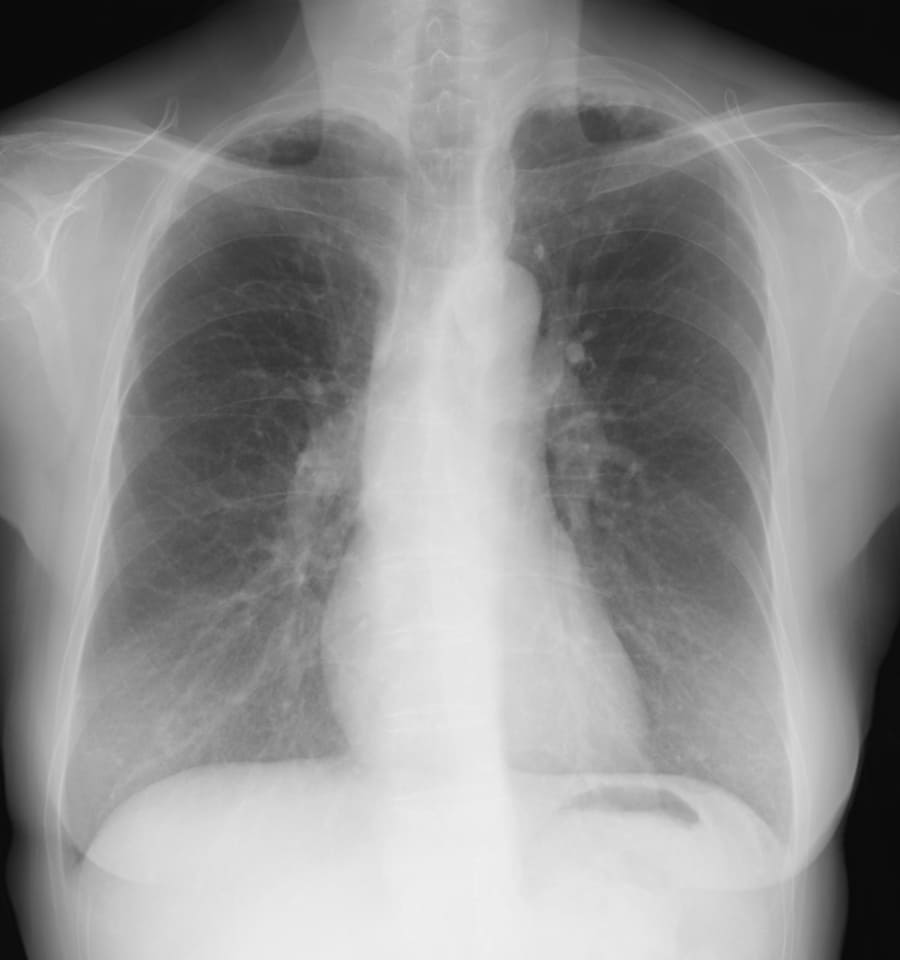

- Q4 呼吸困難を訴える60代女性(事務職)

呼吸困難を訴える60代女性(事務職)

DATA 1| X 線検査結果